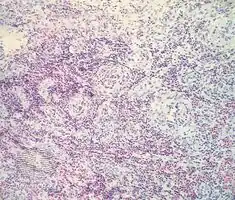

Epithelioid haemangioma is a non-cancerous tumor typically found in skin and soft tissue of usually the head and neck region, where it presents with reddish-pink itchy painful bumps.[1] It can occur in bone as a type of vascular tumor of bone, where it can give rise to pain and swelling.[2]

It is made up of well-formed blood vessels lined by lymphocytes and eosinophils (types of white blood cells).[1]

Angiolymphoid hyperplasia with eosinophilia/pathology